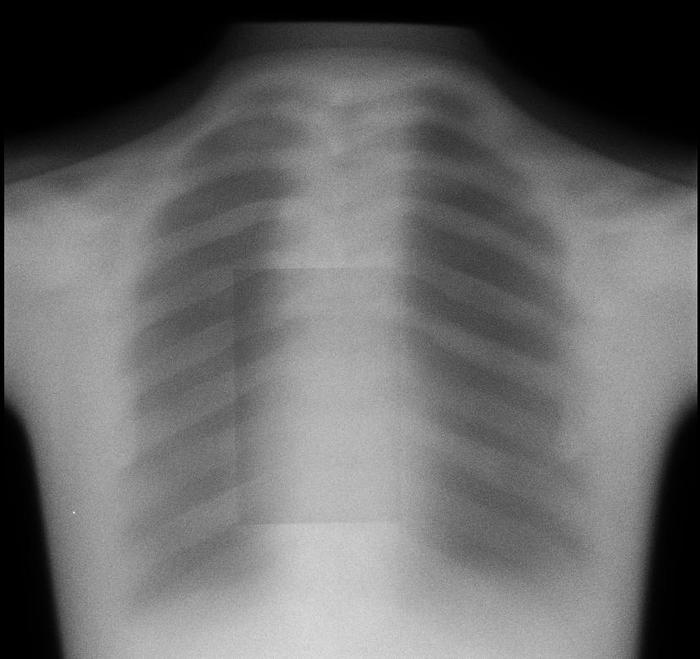

Dr. Ankit I. Mehta’s lab at the University of Illinois at Chicago (UIC MLI) specializes in “the surgical treatment of complex spinal conditions including tumors, degenerative and spine diseases”, among which are corrective surgeries which require screws to be placed in patients’ spines to help correct vertebrae alignment. X-rays are taken at the location of any inserted screws at two occasions - one relatively closer to the operation and another later on - so that movement in screws and/or vertebrae can be monitored over time. At each time, two x-rays are taken: one from the patient’s side (lateral view) and another from the back (AP view). In addition to verifying operation success, the “post” x-rays can help diagnose spinal issues that may have occurred as a result of an operation, such as pseudarthrosis.

For both the lateral and the AP views, there are two separate sources of motion that could contribute to differences between the “pre” and “post” images: movement of the patient and the ovement of the spine and/or screws. The camera itself has preset positions for both views, with millimeter-level noise between separate images that can be effectively ignored. As the movements of the patient are extraneous, they introduce noise that makes it difficult to evaluate patient progress and diagnose any potential issues (e.g. pseudarthrosis) that may cause major health risks. As a result, a patient that may come in after their operation to diagnose why they haven’t seen the expected improvement may require additional x-rays which delay the process, which could result in any medical conditions worsening or potentially another operation being required.

We will create an algorithm enabling users to upload both the “pre” and “post” images, realign/manipulate them, and eliminate noise induced by movement of the patient. By doing so, the lab will be able to make more accurate diagnoses and prognoses of their patients. Having specific, quantitative data on the relative positions and movements of screws and vertebral bodies of interest would help patients to make the best of their own and the lab’s time and diagnose any complications earlier for better health and less cost to the patient.